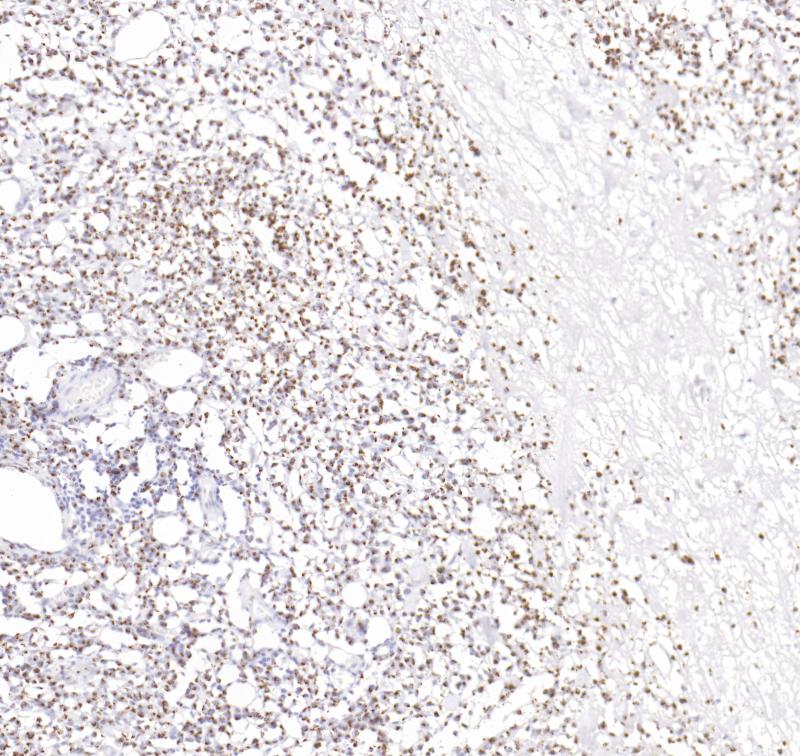

FOXP1 重组兔单克隆抗体

阳性对照

扁桃体

亚细胞定位

细胞核